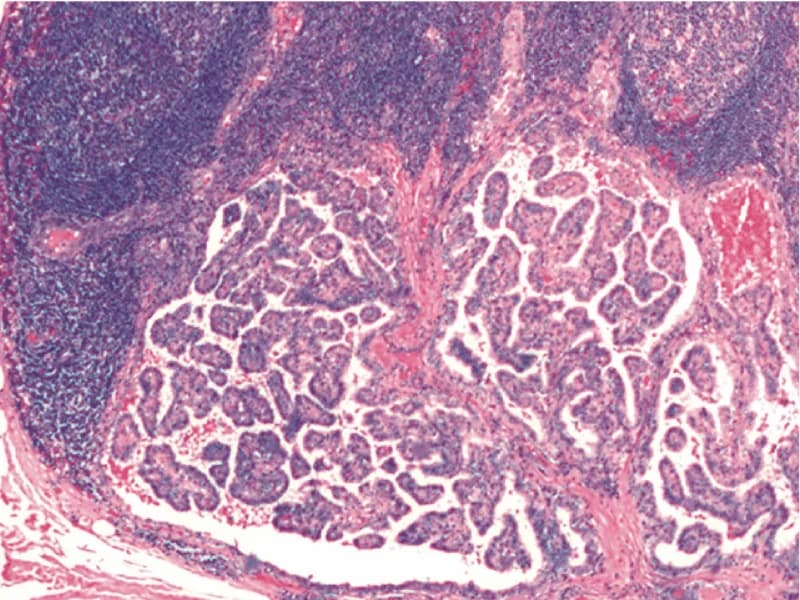

Fato #3: Tipo papilífero (90%) é o mais curável

Carcinoma papilífero (90%)

Características:

- Mais comum (90% dos casos)

- Cresce lentamente (anos)

- Metástase: linfonodos cervicais (30-40%)

- Raramente metástase distante (2-5%)

- Sobrevida 30 anos: 95%

Variantes:

- Clássica (80%): melhor prognóstico

- Folicular (10%): prognóstico similar

- Esclerosante (5%): mais metástase linfonodal

- Células altas (rara): mais agressiva